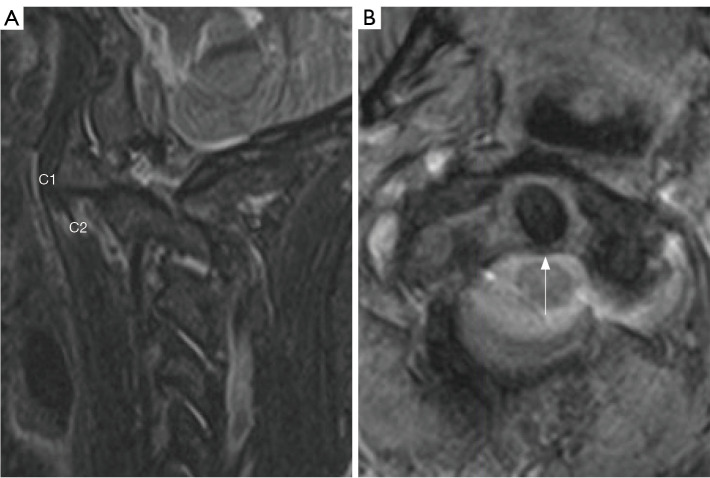

Atlantoaxial rotatory subluxation (AARS) in the adult population is primarily trauma-induced. Conservative and surgical treatments have both been used successfully in treating AARS. In cases where AARS cannot be reduced by conservative measures, open reduction and fusion is the conventional treatment approach. This report details a novel approach for treating adult AARS, where an open reduction was performed without instrumentation or fusion. The patient, a 48-year-old female involved in a high-speed vehicular collision, initially underwent conservative treatment with Gardner Wells Tongs and manual traction. Despite these efforts, X-ray and computed tomography (CT) scans indicated persistent subluxation. Subsequently, the patient was taken to the operating room, where successful open reduction was achieved without the need for fusion or instrumentation. Preoperative imaging revealed rotatory subluxation of C1-2 with a comminuted and displaced fracture of the right C1-2 facet joint and a nondisplaced fracture of the base of the occiput. The surgical technique involved precise manual manipulation using a Cloward spreader and real-time assessment with O-arm 3D X-ray tomography to ensure successful reduction. The absence of significant laxity or instability during intraoperative testing led to the conclusion that fusion was unnecessary. This approach minimizes invasive tissue dissection and preserves natural cervical range of motion (ROM). Postoperatively, the patient was asymptomatic with no joint instability and demonstrated satisfactory alignment at follow-up.